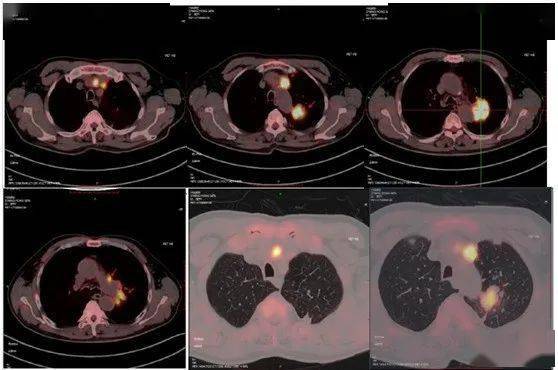

因声音嘶哑就诊发现肺腺癌晚期

肺腺癌晚期肿瘤图片

右肺腺癌术后3年肺内转移结节射频消融病例分享

肺腺癌广泛胸膜转移,胸腔积液,治疗2年后病灶缩小(6次住院)